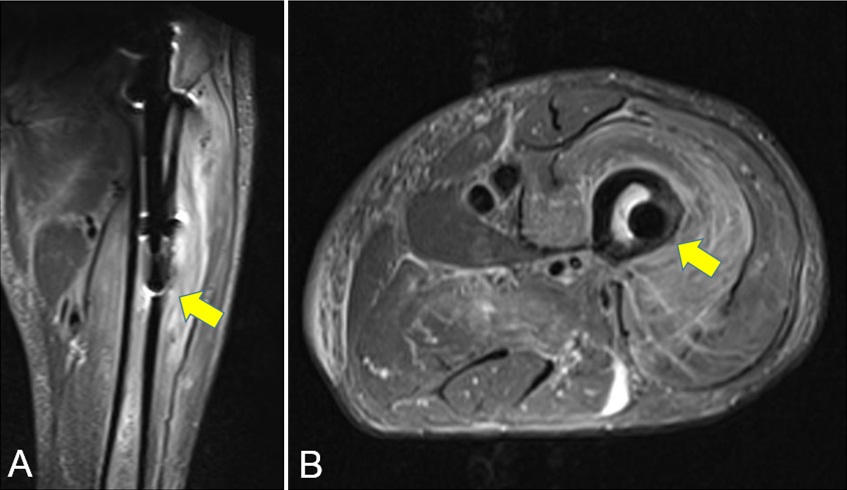

Penetración de la cortical anterolateral en fracturas de fémur proximal tratadas con clavos endomedulares cortos Reporte de dos casos. [Penetration of anterior-lateral cortex in proximal femur fractures treated with short intramedullary nails Report of two cases].

7. Ostrum RF, Levy MS. Penetration of the distal femoral anterior cortex during intramedullary nailing for subtrochanteric fractures: a report of three cases. J Orthop Trauma 2005;19:656-60.